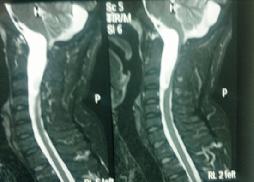

Intradural Neurofibroma

Large Conus Ependymoma